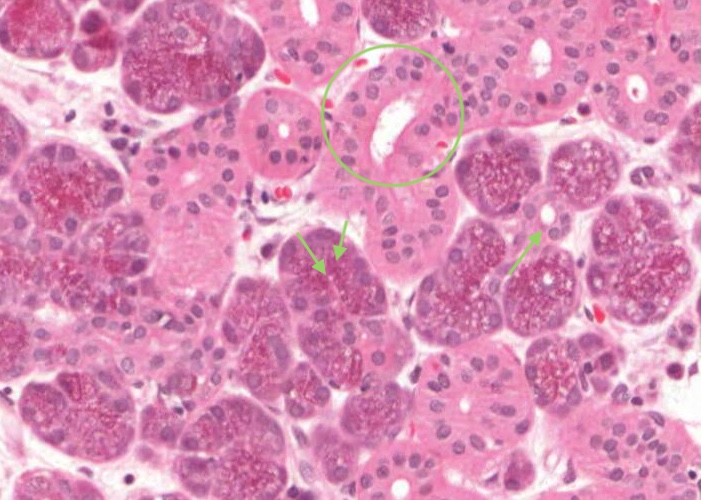

The mucous-secreting cells are palely stained, with nuclei flattened against the cell bases. They are closely related to the goblet cell. The serous-secreting cells stain vigorously with hematoxylin. Their basophilia suggests vast quantities of ribosomes and, indeed, this cell type makes enzymes for export in a watery secretion. Note that small groups of serous cells often cap the end of mucous acini. These half-moon-like figures are called serous demilunes.